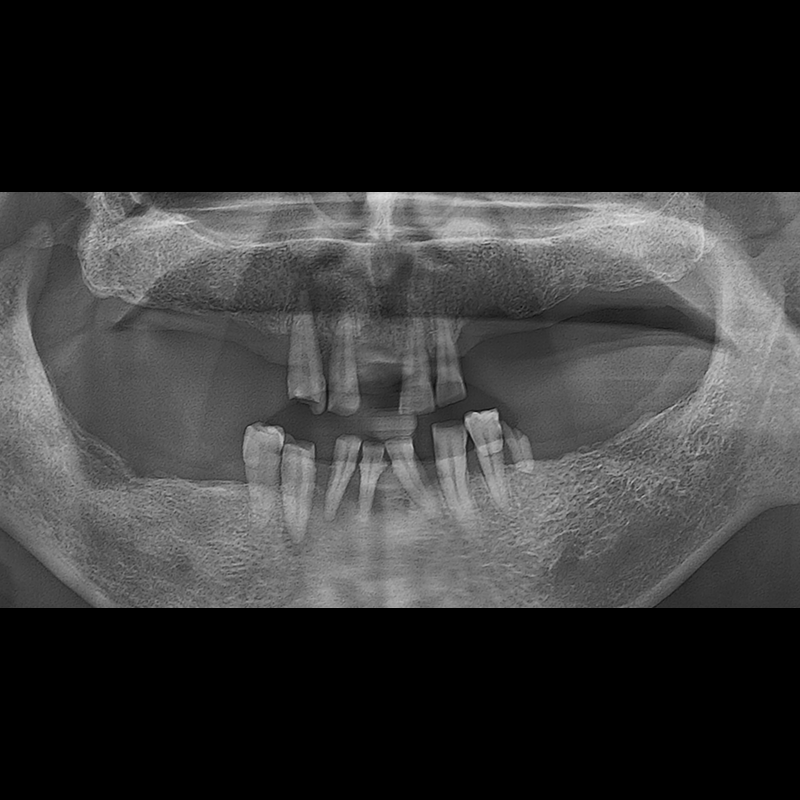

BEFORE AFTER

임플란트 전후사진 2025.05.30

결손된 치아 부분과 살리기 힘든 치아 위치에 임플란트를 식립하였습니다.